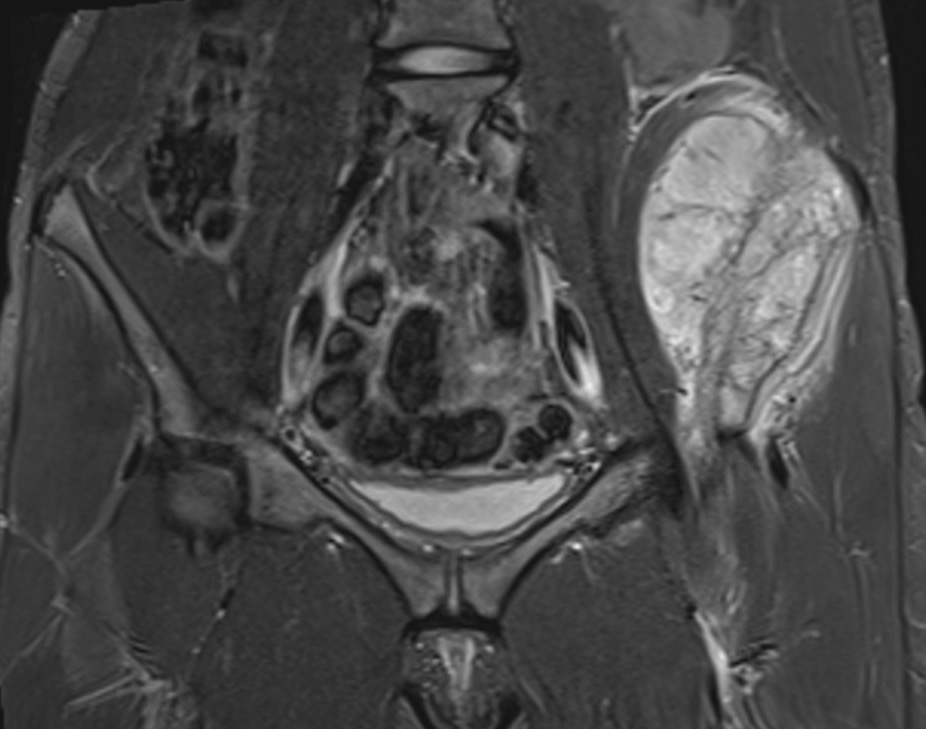

Pelvis

Ewings pelvisAcetab Met

Iliac crest Ilioinguinal approach

Anterior column Watson - Jones through G medius

Posterior column Kocher - Lagenbeck through G maximus

Pubis Pfannenstiel approach

Ischium Posterior approach

Sacrum Direct posterior approach